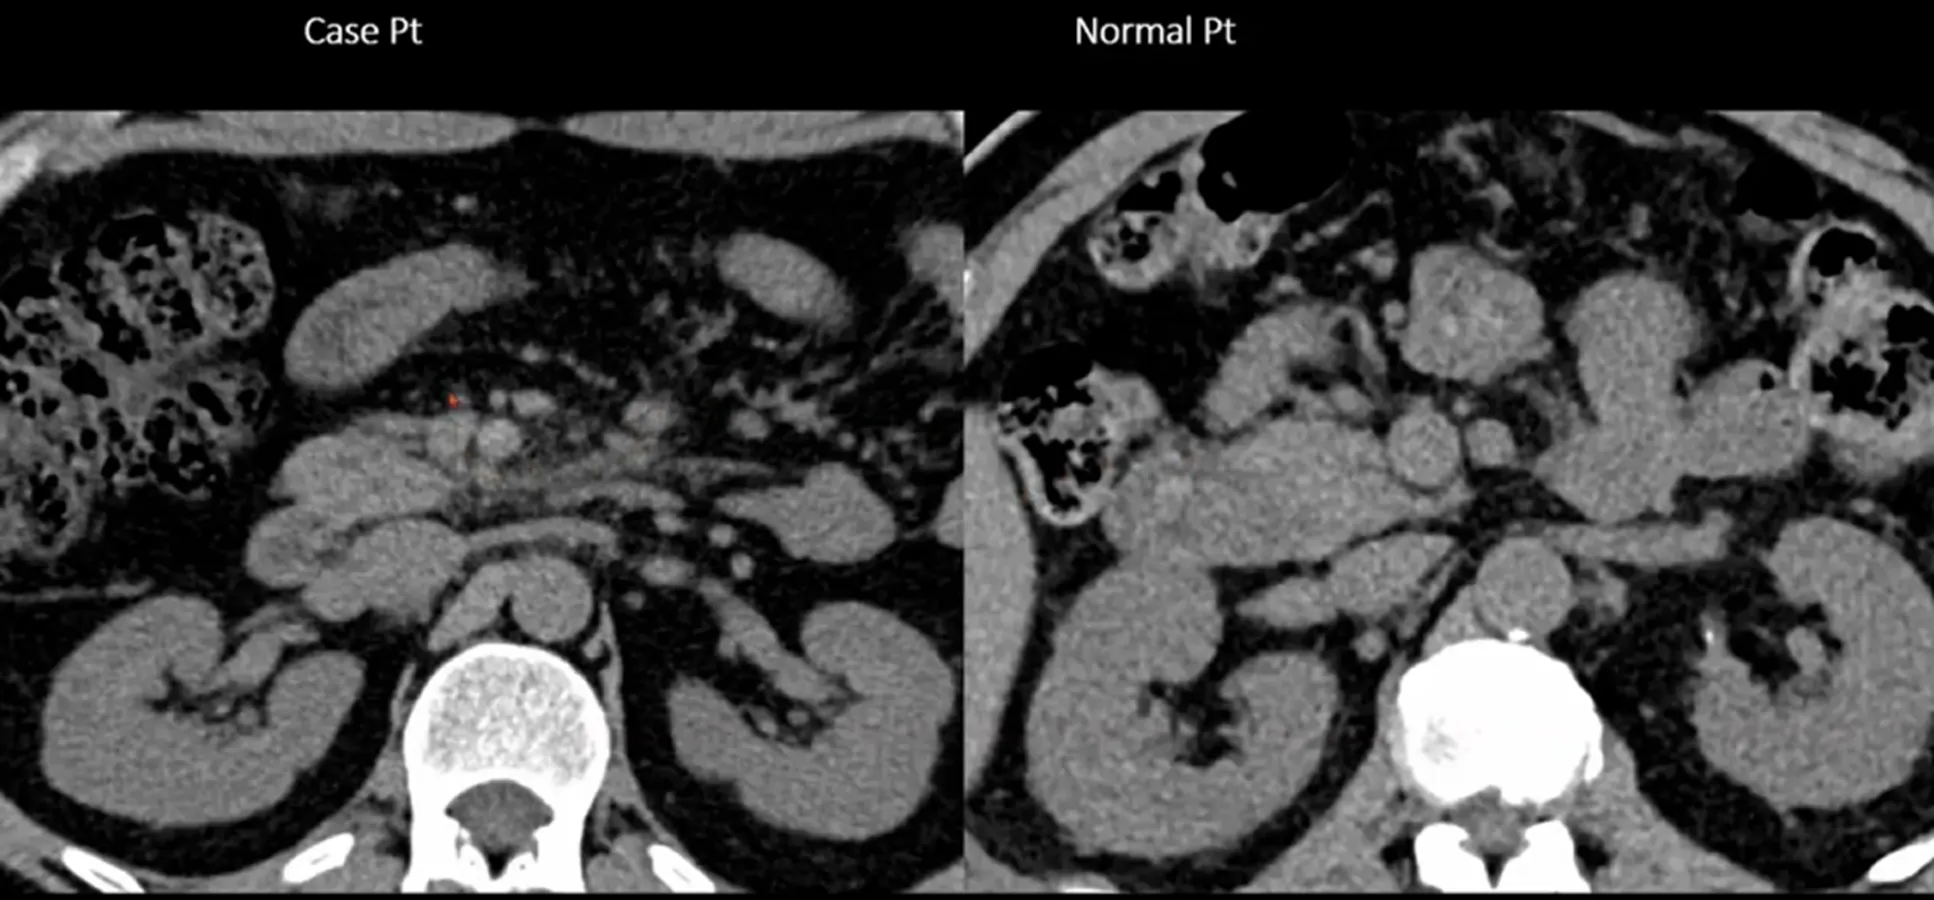

Take home message

1.

Master normal anatomy, normal findings

2.

Compared with other part of body (Asymmetry 확인)

3.

Compared with previous image

4.

Compared with another Patient

5.

Most important clue is clinical setting

6.

You can find mor clues as much as you know (아는 만큼 많이 보인다)